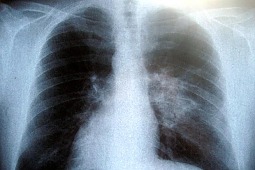

Innowacje diagnostyczne: rak płuca wykryty w badaniu krwi

Rak płuca to najczęstszy nowotwór złośliwy, na który umiera rocznie na całym świecie 1,3 mln osób. Francuscy naukowcy opracowali metodę, która bardzo wcześnie wykrywa raka płuc. Jak informują nawet kilka lat wcześniej, zanim nowotwór uwidoczni się na zdjęciach rentgenowskich. Wszystko dzięki badaniu krwi. Odkrycie może w znaczącym stopniu zwiększyć liczbę wyleczeń i stanowić przełom w walce z tym nowotworem.